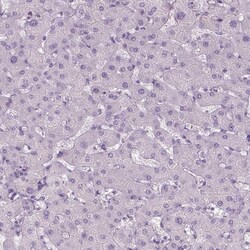

Invitrogen™ TMEM16B Polyclonal Antibody

Calcium-activated chloride channels (CaCC) are present in many cell types and mediate physiological functions such as epithelial secretion, sensory signal transduction, and smooth muscle contraction. Subunits of these CaCC's include the transmembrane proteins TMEM16A and TMEM16B. TMEM16B is predicted to have eight transmembrane domains with both the amino and carboxy termini in the cytoplasm and is expressed in several tissues including olfactory sensory neurons as well as photoreceptors in mammalian retina. Like TMEM16A, TMEM16B is thought to form at least part of CaCC's but has different biophysical characteristics such as voltage dependence and unitary conductance.

| Applications | Immunohistochemistry (Paraffin) |